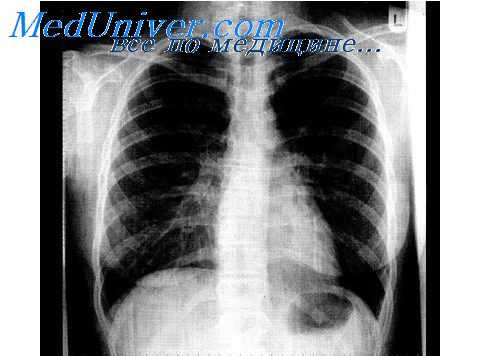

Характеризуя роль нервной системы в развитии воспаления, необходимо остановиться на вопросах сегментарной регуляции воспалительного процесса, а также трофическом влиянии нервной системы на течение воспаления. Данное обстоятельство имеет особое значение при развитии воспалительных заболеваний легких, формировании РДСВ. Показано, что блокирование соответствующих сегментов грудного отдела спинного мозга сопровождается снижением степени выраженности прессорных реакций микрососудов легких и тем самым оптимизацией кислородного обеспечения легочной ткани, снижением концентрации метаболитов, усиливающих деструктивные процессы.